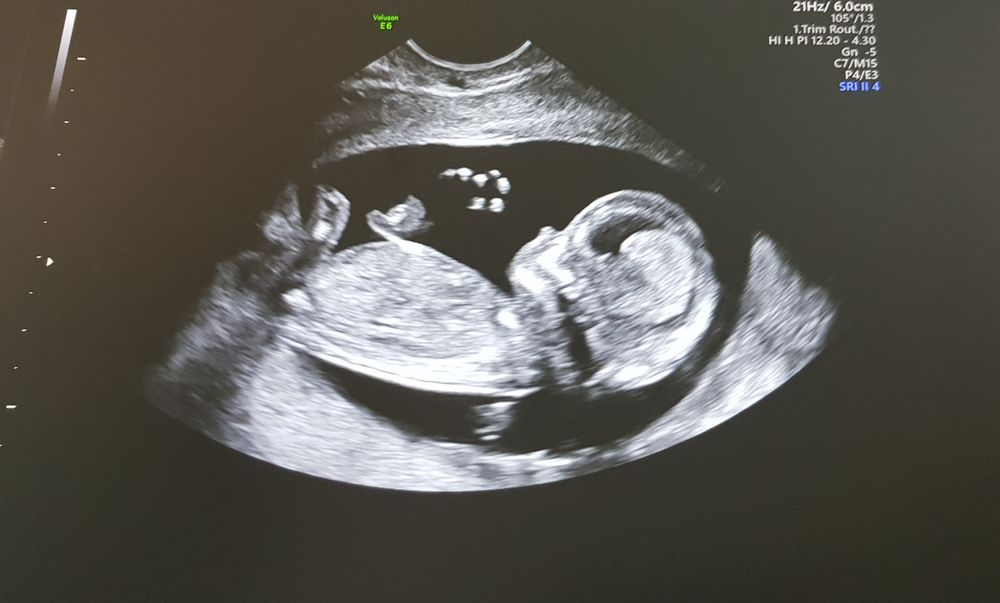

УЗИ 12 нед.

Сейчас уже ощущаю лёгкие движения малыша, чувства странные, пока непонятно)) В 10 нед. купила Доплер, чтобы жить спокойно, штука классная👍 На первом скрининге предположили девочку, на втором посмотрим точно, но нам и не важно, главное чтобы здоровый ребенок был. Последний раз писала когда попала на сохранение с отслойкой, вобщем пролежала почти 2 недельки и снова в строй, очень долго не проходила бежевая мазня, мне сказали так выходит гематома. Вот и все новости🤷🎉